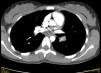

Ante la sospecha de TEP, se deriva a urgencias del hospital de referencia donde se realizan las siguientes pruebas:

Hemograma, bioquímica y gasometría arterial con valores dentro de la normalidad; coagulación: normal salvo un dímero de 8.079; radiografía de tórax: aumento de densidad en base derecha pulmonar; TC torácica (fig. 1): TEP masivo bilateral con trombo a caballo de la bifurcación de ambas arterias pulmonares principales que afectan a la continuación, en el lado izquierdo, a la arteria anterior del lóbulo superior, arteria de la língula y lobar inferior con escasa recanalización periférica. Trombo en arteria pulmonar principal derecha que se continúa afectando a arteria lobar y segmentarias inferiores derechas con escasa recanalización periférica.